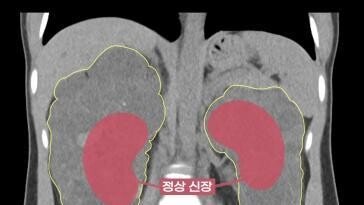

생식세포는 나이가 들면서 감소하게 되는데 만 35세 이후로 더 빠른 속도로 감소한다. 난자의 질도 저하된다. 남아있는 생식세포의 수를 반영하는 지표를 난소 예비력이라고 하는데 호르몬검사, 난소나이(AMH)검사 및 동난포수(AFC) 검사를 통해 확인할 수 있다.

난소의 예비력은 폐경 몇 년 전에 이미 떨어지기 때문에 현재 생리를 하고 있는 것이 곧 임신이 가능함을 의미하는 것은 아니다. 난소 예비력이 저하되기 이전에 건강한 생식세포를 보존해야 할 필요성이 있고 이에 대한 대안이 바로 ‘난자냉동’이다.